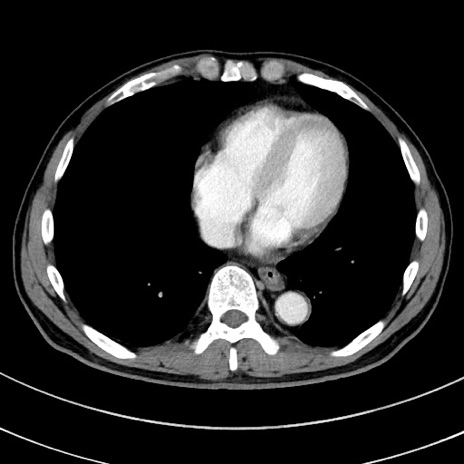

症例8(横断像)

【症例】 60歳代男性

【主訴】 黒色吐物

【現病歴】 4日前から嘔気自覚、2日前の朝食後にも嘔気あり、自分で手で嘔吐反射起こし嘔吐したところ血が混ざっていたため受診。

【既往歴】 5年前汎発性腹膜炎を伴う急性虫垂炎で手術、高血圧、前立腺肥大症、高脂血症

【身体所見】 腹部正中に手術癩痕あり 腹部平坦・軟圧痛なし膨満感あり

【データ】WBC 8400、CRP 4.54